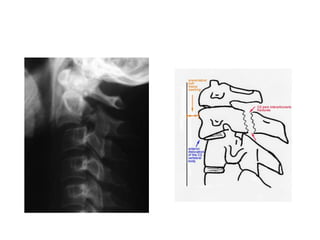

RADIOLOGY

Alignment

Lateral view

Top of T1 visible

Three smooth arcs

maintained

Vertebral bodies of uniform

height

Odontoid intact and closely

applied to C1

AP View

• The height of the cervical

vertebral bodies should be

approximately equal

• The height of each joint

space should be roughly

equal at all levels

• Spinous process should be

in midline and in good

Odontoid View

• An adequate film should include

the entire odontoid and the lateral

borders of C1-C2.

• Occipital condyles should line up

with the lateral masses and

superior articular facet of C1.

• The distance from the dens to the

lateral masses of C1 should be

equal bilaterally.

• The tips of lateral mass of C1

should line up with the lateral

margins of the superior articular

facet of C2.

• The odontoid should have

uninterrupted cortical margins

blending with the body of C2.

Swimmers view

Key Things to Identify

• Predental space – should be 3mm or less

• Prevertebral soft

tissue swelling

– May be due to

hematoma from a

fracture

– Soft tissue swelling

may make fracture

diagnosis difficulty

• Disc spaces should be the equal and

symmetric